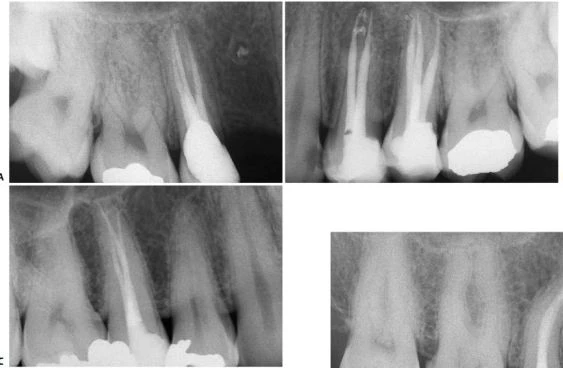

Trên X-quang có thể thấy chân răng hơi cong nhẹ theo chiều gần xa hoặc ngoài trong (hình 5.41).

Hình 5.41. A. Phim X-quang trước điều trị của răng cửa giữa hàm trên bên phải. Lỗ chóp nằm trên cùng một mặt phẳng trên đường đi của tia X: nó có thể đối diện với mặt trong hoặc mặt ngoài. B. Phim X-quang thứ hai chụp theo hướng gần-xa cho thấy đoạn cong đối diện với mặt ngoài. Việc điều trị tủy được hoàn tất, giữ nguyên góc chụp cho phép nhìn thấy được điểm cuối cùng trên X-quang của ống tủy. C. Phim sau điều trị. Lưu ý rằng chỉ với góc chụp này mới thấy được hình ảnh tổn thương nhỏ tại chóp chân răng. D. Phim sau điều trị được chụp theo tiêu chuẩn hình chiếu. Lưu ý rằng vật liệu trám ống tủy dường như bị ngắn đi chừng 2mm và tổn thương cũng đã lành.